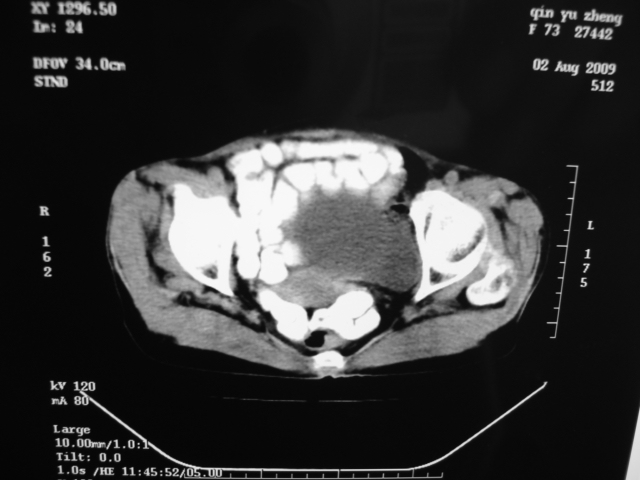

同事奶奶,73岁,腹痛一年,夜晚较重,潜血+++,拒绝增强,考虑左肾ca并腹膜后转移;请各位老师帮忙看看,谢谢!

左肾癌侵及输尿管上段,腹膜后多发淋巴结转移,脾脏钙化灶。至于潜血+++,要考虑消化道病变,本次ct片肠腔未见明显异常。

1)考虑左肾癌侵犯肾盂并腹膜后淋巴结转移。2)脾脏钙化灶。

考虑左肾癌侵犯肾盂并腹膜后淋巴结转移。